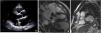

In view of the patient's hemodynamic instability, urgent electrical cardioversion was required, following which the patient was asymptomatic. The ECG showed sinus rhythm with non-specific ventricular repolarization alterations. Laboratory tests revealed no abnormalities. The transthoracic echocardiogram showed severe left atrial dilatation, prosthetic ring without signs of dysfunction, preserved LV function, and an image suggestive of MAD, with a distance of 15 mm and evidence of undulating movement of the inferolateral LV wall and stretching of the chordae tendineae (Figure 2A). Coronary angiography excluded coronary disease. The patient was referred for cardiac magnetic resonance imaging (CMRI), which revealed dyskinesia of the basal segment of the inferolateral wall with severely reduced thickness, as well as a perfusion defect and transmural late enhancement. This was interpreted as indicating possible fibrosis in the context of MAD (Figure 2B and C).

(A) Transthoracic echocardiogram in parasternal long-axis view showing mitral annular disjunction (yellow arrow); (B) cardiac magnetic resonance imaging, 3-chamber cine view, showing mitral annular disjunction (yellow arrow); (C) cardiac magnetic resonance imaging, short-axis view, showing transmural late enhancement in the basal segment of the inferolateral wall.